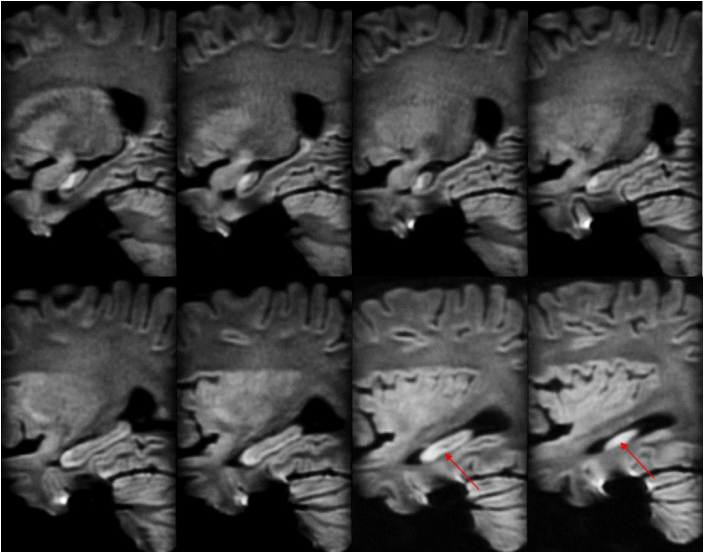

除此之外,海马的信号怪怪的,是什么?所以,我们加扫海马矢状位小视野弥散。

•Sag FOCUS DWI 1000,FOV = 22 × 8.8cm,2.0 / 0.0 mm

海马最外层呈弥散受限表现,但是总感觉雾里看花,并不清晰。我们还能做什么?